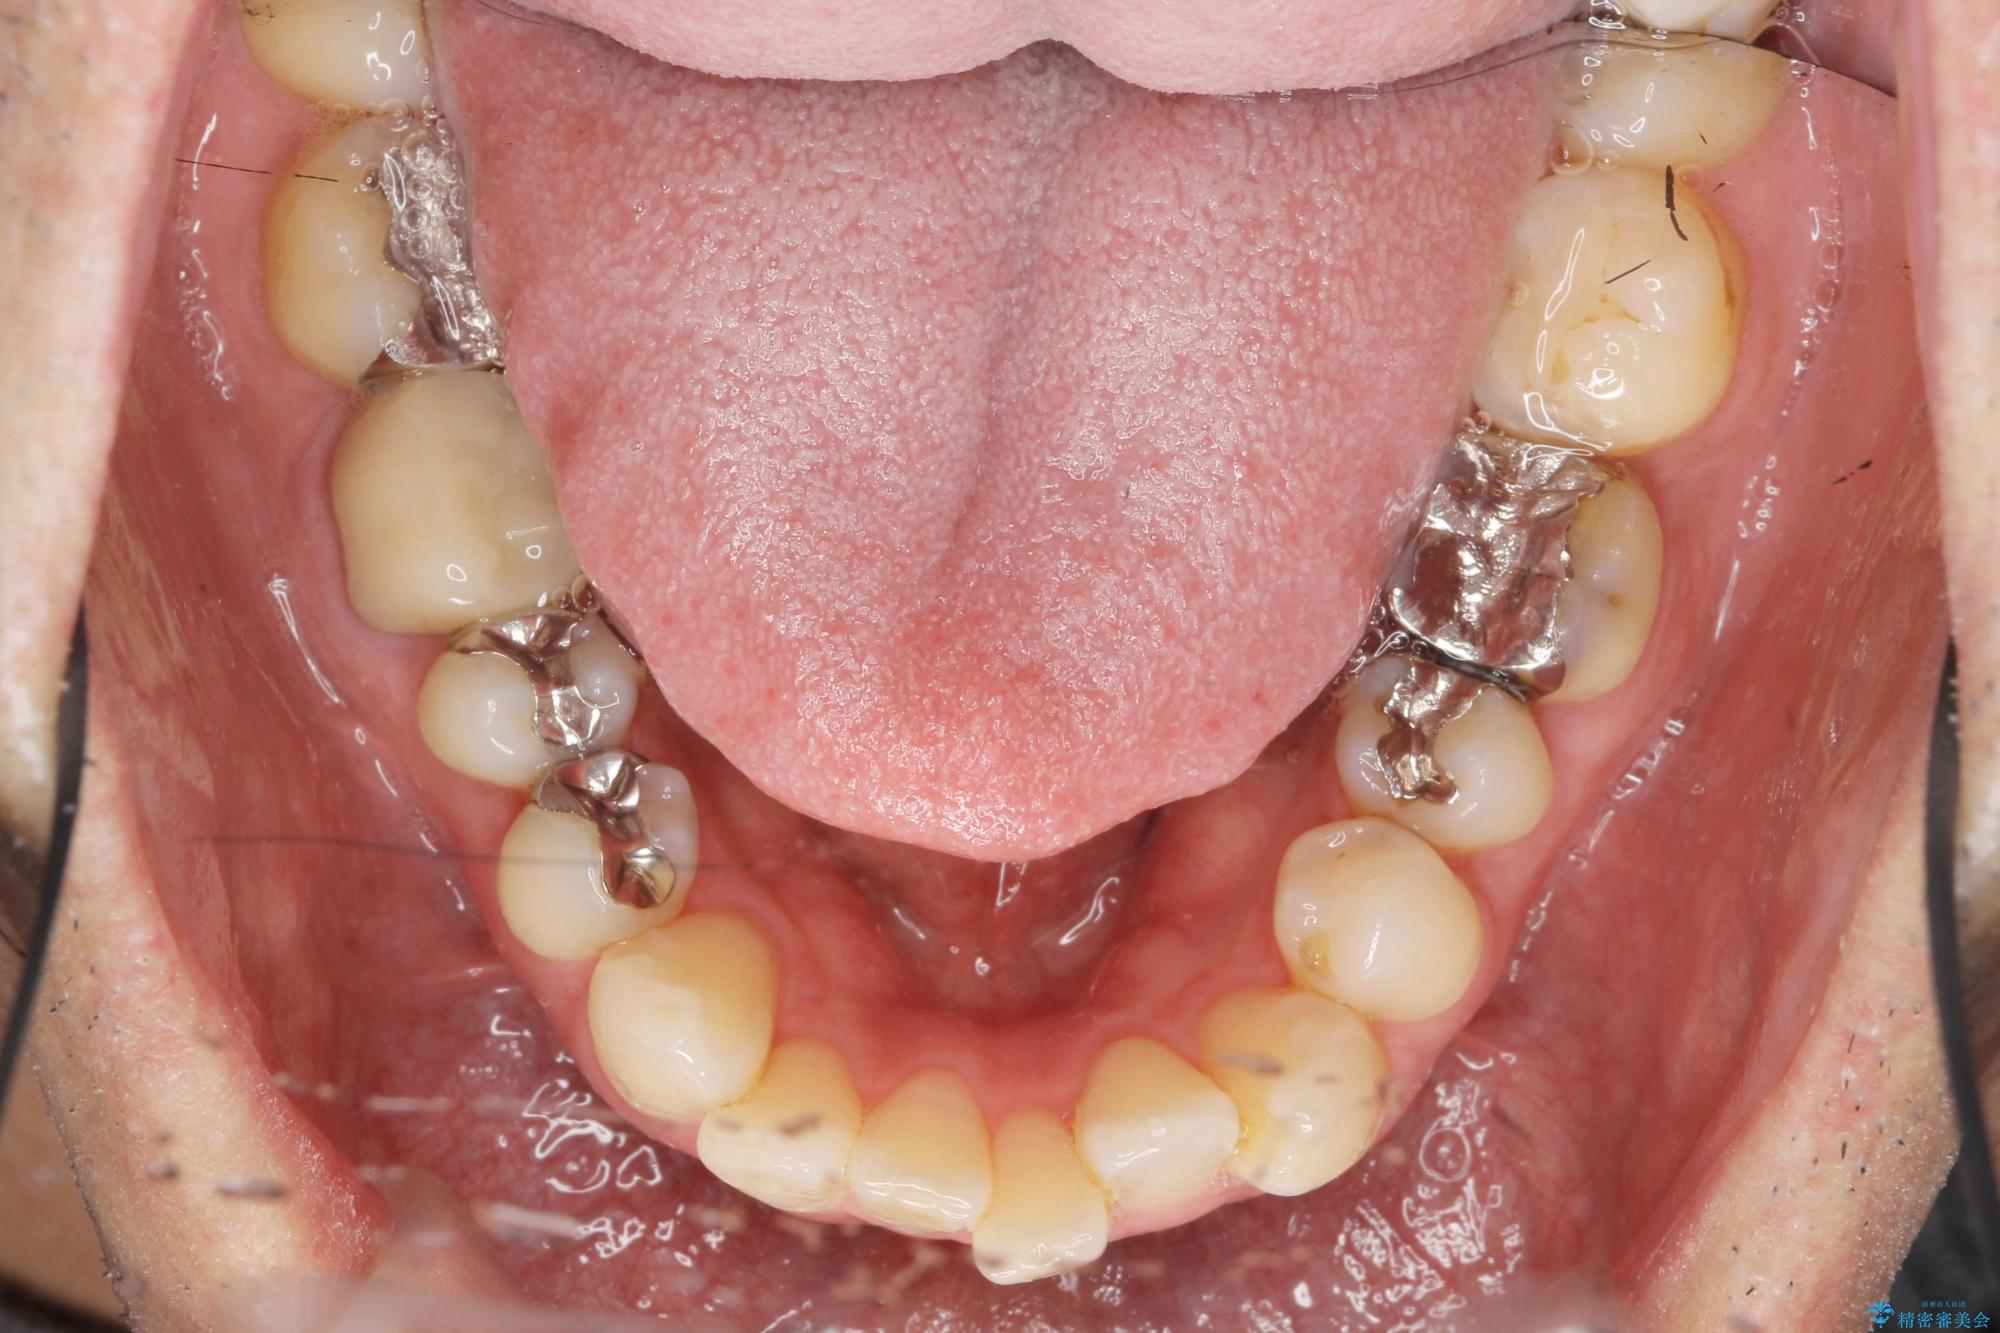

- 突き出た前歯の角度の改善と虫歯治療の改善を求めて来院されました。

虫歯を除去したのち、マウスピース矯正治療を行い、歯並びやがたつきを改善したのち、セラミックに置き換えることで審美性の向上を計画します。